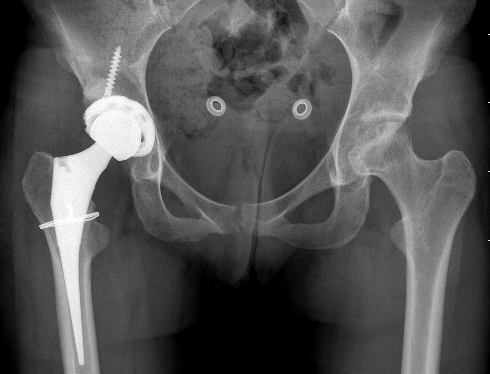

Operative Management Stage III / IV (Collapse)

Options

Osteotomy

Limited resurfacing

THA

Total hip arthroplasty

Issues

? Failure rate higher than in age matched OA patients

- also worse if caused by ethanol / steroids

Results

Australian Joint Registry 2022 Annual report

- 580,000 THA

- THA overall 20 year revision rate 11%

- THA for OA overall 20 year revision rate 8%

- 14,000 AVN (3% overall)

- THA for AVN 20 year revision rate 12%